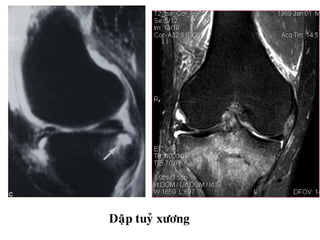

Daäp tuyû xöông

Baker’s cyst